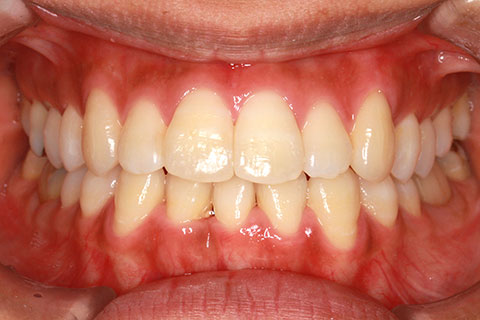

ハーフリンガル矯正4:上の歯のみ舌側矯正で治療(矯正期間24ヶ月)

- 年齢・性別

- 23歳女性

- 治療期間

- 2年0ヶ月

- 抜歯

- 上下4番抜歯

- 治療費

- 110万円

- 備考

- マルチブラケットを用いた矯正治療

- 治療内容

- 施術の副作用(リスク)

- 表側矯正と比較して、前歯のラビッティング(舌側傾斜)を起こしやすい。